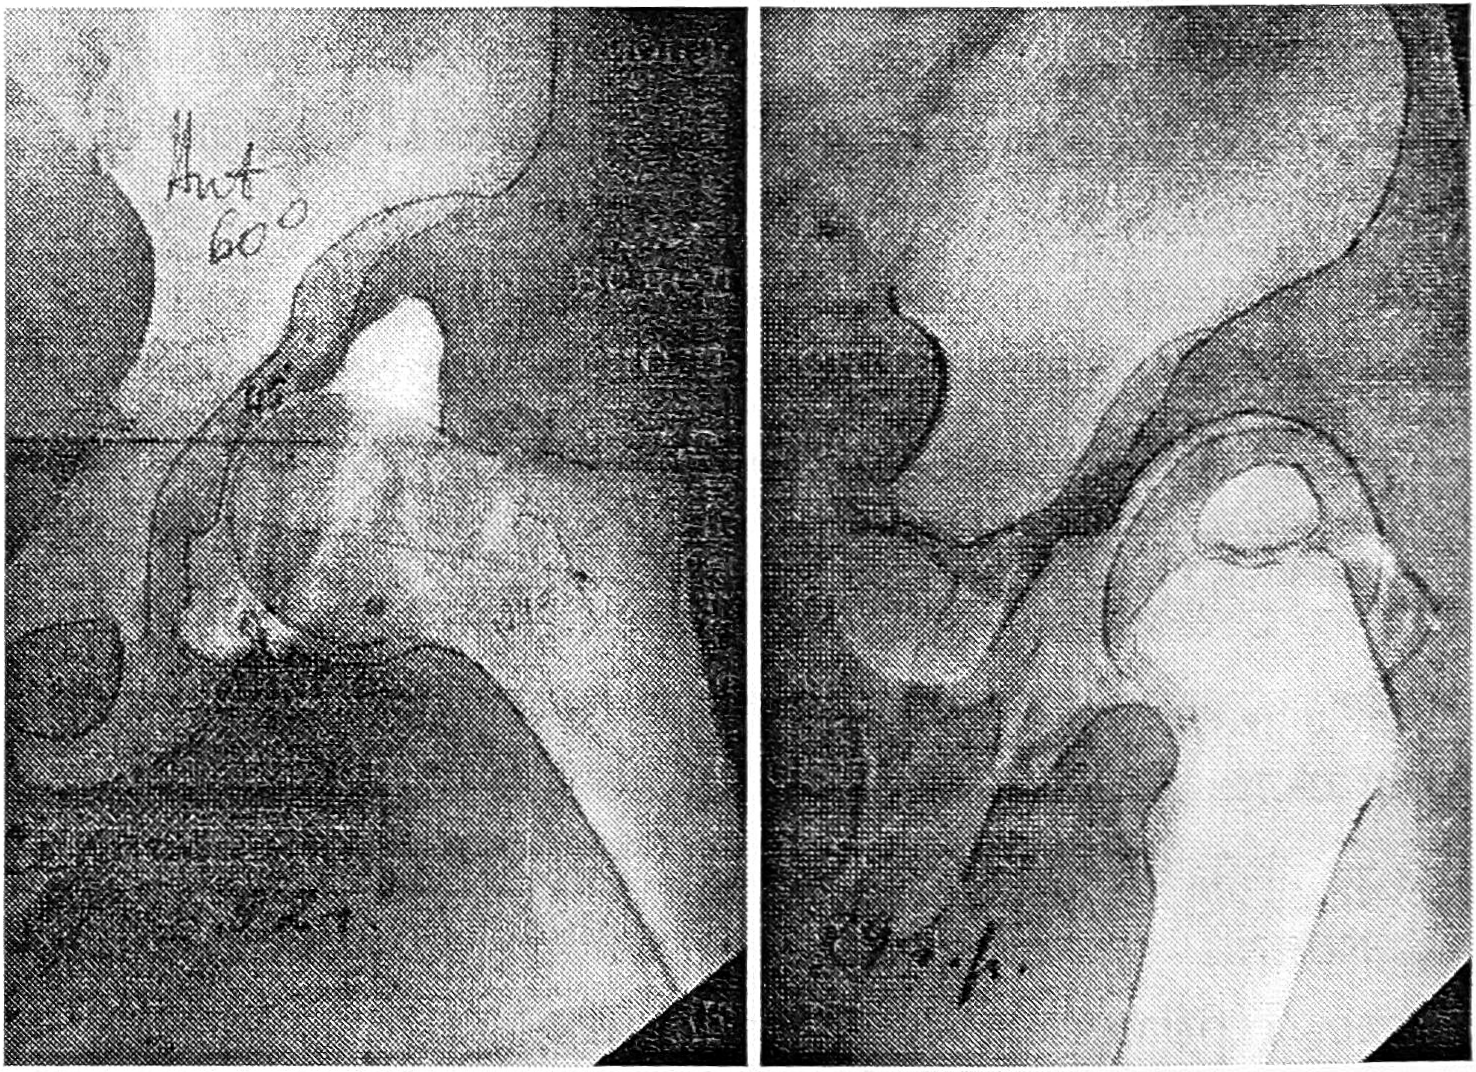

— резкое сужение перешейка капсулы, выраженное в обеих проекциях (рис. 2);

— низкий маргинальный вывих с очевидным дополнительным повреждением недоразвитой крыши впадины вследствие подвижности головки по борозде скольжения (рис. 3).

Рис. 2. Больная Е. 2 лет. Резко сужен перешеек капсулы, лимбус подвернут и фиксирован к дну впадины, ацетабулярный индекс 45°; при внутренней ротации бедер картина не изменяется.

Рис. 3. Больной К. 3 лет. Низкий маргинальный вывих, впадина утолщена, ацетабулярный индекс 45°, лимбус раздавлен или подпаян к дну впадины, головка бедра перемещается по борозде скольжения.